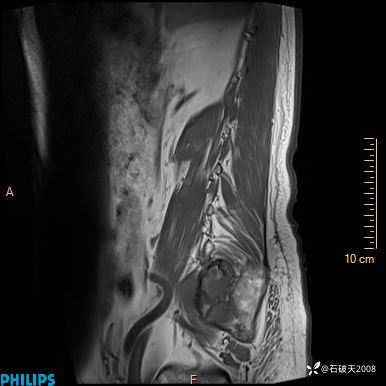

2023年3月份MRI影像

T2矢状位